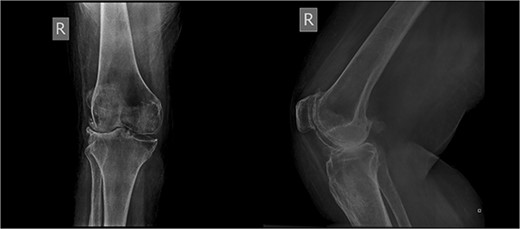

An 86-year-old female patient with a body mass index (BMI) of 31.2 presented to our outpatient department with severe right knee pain. Physical examination revealed a mechanical block of the knee, limiting its range of motion (ROM) between 10° and 55° of flexion. Plain knee radiographs showed grade 4 knee osteoarthritis (OA) in the Kellgren–Lawrence scale (Fig. 1).

The patient underwent a medial-pivot design TKA (Evolution Medial-Pivot Knee System, Microport, China). Intraoperatively, a full ROM was achieved only after extensive soft tissue and bone releases. The extension gap was limited by significant hamstring spasticity, and a proper extension gap was attained after additional anterior femoral cut. Early postoperative recovery was uneventful (Fig. 2). On the third postoperative day, the patient complained of severe knee pain accompanied by excessive swelling during kinesiotherapy. Clinical examination showed a posterior sag sign at 30° of flexion (Fig. 3). No signs of neurovascular deficit were obvious. A knee X-ray revealed posterior TKA dislocation and a small, non-displaced femoral fracture (Fig. 4). The tibial component was reducible, but redislocation occurred with the knee extended over 90°, indicative of severe instability. Laboratory investigations, including erythrocyte sedimentation rate and C-reactive protein, were normal. A knee arthrocentesis was performed with no substantial findings. Two botulinum toxin injections (200 IU) to the hamstrings were performed without improvement. Local muscle hypertonia was evaluated through a neurological examination and a brain computed tomography scan, with no remarkable findings. The patient’s history included intramedullary nailing of the right femur due to an intertrochanteric fracture 8 months before the TKA.